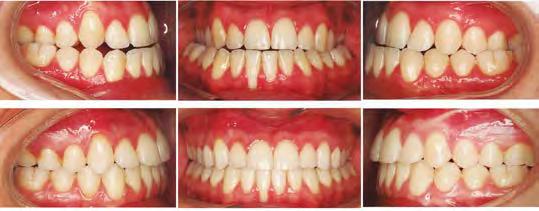

–Corticotomías y Ortodoncia. Ampliando límites del movimiento dental, por la Dra. Aranzazu Senosiain y cols. [50]

–Tratamiento de un caso de Ortodoncia y Cirugía Ortognática con placas preformadas y tecnología 3D, por la Dra. Elena Bonilla Morente y cols. [62]

–Uso del anclaje esqueletal como alternativa eficiente en el manejo ortopédico de clases III por deficiencia de maxilar superior, por el Dr. Carlos Becerra y cols. [74]

–MARPE, una alternativa a la disyunción en el paciente adulto, por el Dr. Enrique Solano y cols. [88]